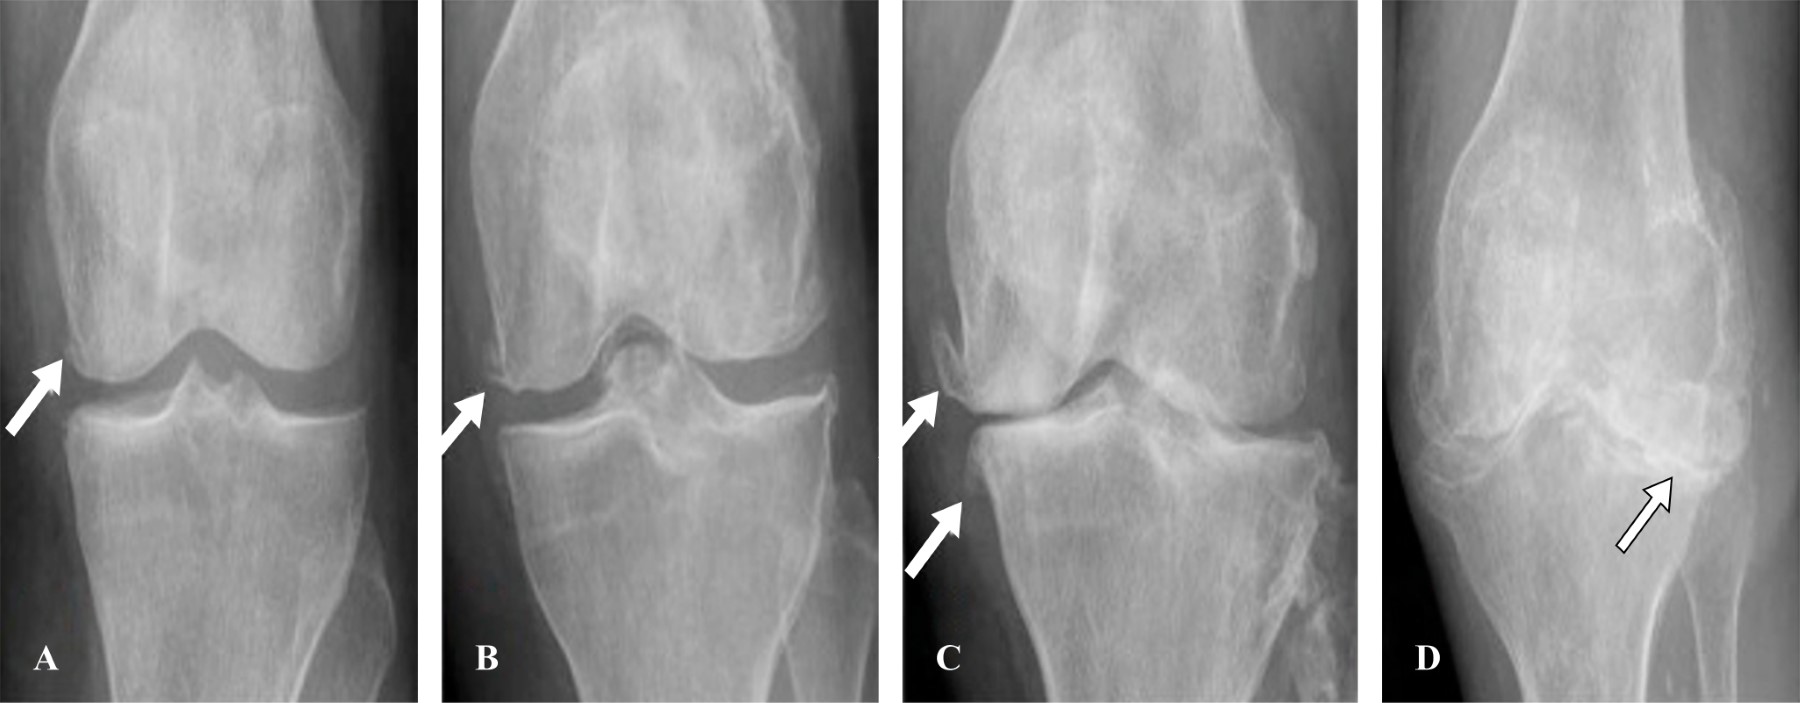

La artrosis se puede clasificar radiográficamente de acuerdo con la escala de Kellgren/Lawrence, así como la relación en el proceso patogénico. En un estudio realizado por J. H. Kellgren y J. S. Lawrence en 1956, se realizó un análisis entre las diferencias y las interpretaciones radiológicas para llegar a determinar grados, y estadificar el tipo de desgaste articular en la artrosis. Este proceso tendría evolutivamente cinco fases:

Fase 0: ausencia de osteofitos, estrechamiento o quistes; fase 1: osteofitos únicamente; fase 2: osteofitos pequeños, estrechamiento de la interlínea moderado, puede haber quistes y esclerosis; fase 3: osteofitos claros de tamaño moderado y estrechamiento de la interlínea; fase 4: osteofitos grandes y pérdida de la interlínea articular y presencia de geodas mismas fases que hasta hoy en la actualidad se han utilizado para determinar el diagnóstico radiológico del desgaste articular, así como la base inicial para el tratamiento de dicha patología (Figura 2).